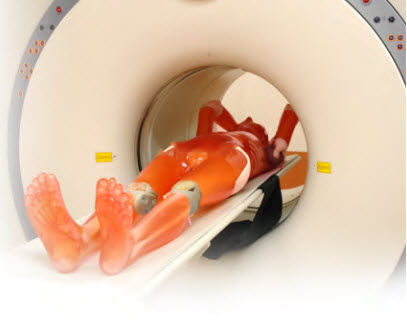

模型1:1 真人等比例大小,無(wú)論是骨骼還是內(nèi)臟器官都擁有與人體相同的X 線吸收率。在普放設(shè)備與CT 下都能得到與真人高度相似的透視圖像,并且支持3D 影像重建??蓜?dòng)式關(guān)節(jié)設(shè)計(jì),允許按照臨床實(shí)際擺放拍攝體位,且各個(gè)部位都可快速的分解拆卸,單獨(dú)使用??捎糜谟跋窠虒W(xué),訓(xùn)練技師,圖像質(zhì)量管理,設(shè)備研發(fā)等多種用途。領(lǐng)先材料,不含任何有害物質(zhì)以及金屬材料。

成人男子全身大小,長(zhǎng)約165cm,重量50kg

可用于普放設(shè)備拍攝,也可用于CT建模。

適用于普通X射線平片拍攝,CT計(jì)算機(jī)斷層掃描裝置,及三維圖象重建用途的多功能影像模型,可用于各式讀片訓(xùn)練和解剖教學(xué)、設(shè)備例行檢測(cè)及校對(duì)和日常影像質(zhì)量評(píng)估。